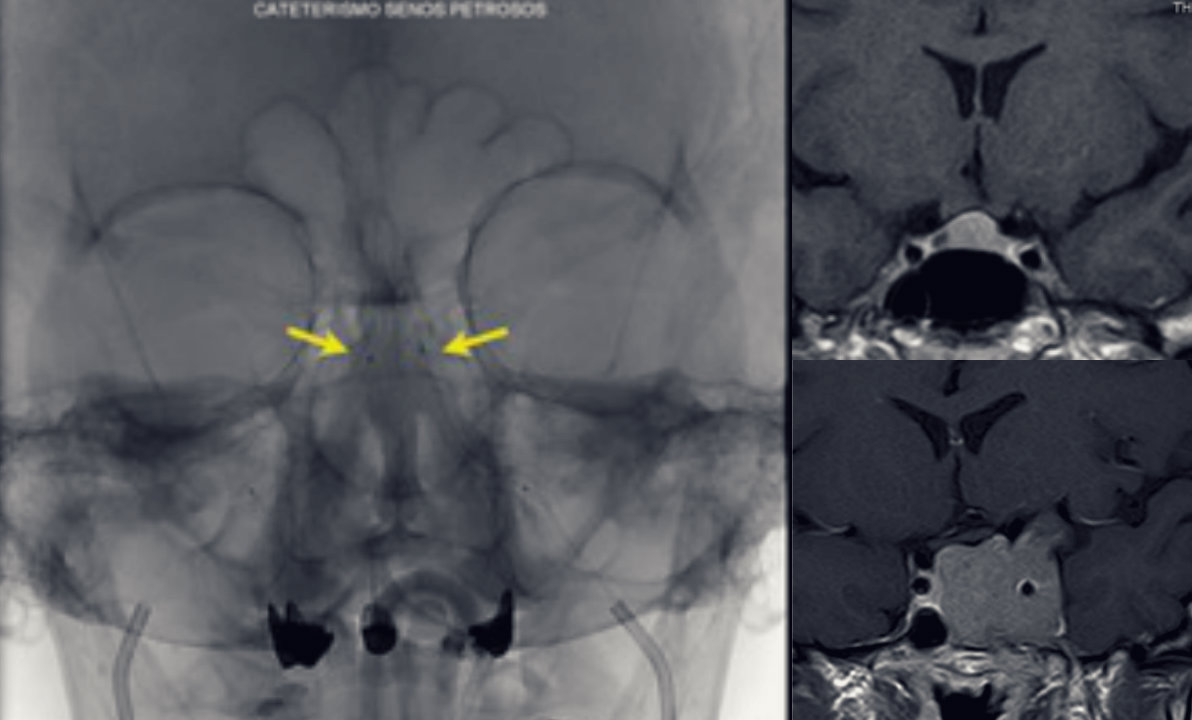

El especialista de la Clínica Alemana vislumbra diversos desafíos para esta patología. Entre ellos, aquellos adenomas corticotropos muy pequeños que no se logran identificar con estudios de resonancia convencionales y relata que en el Instituto de Neurocirugía se está desarrollando un protocolo de resonancia magnética modificado que podría aumentar la pesquisa de la lesión antes de la operación. Otro desafío son los tumores funcionantes invasores al seno cavernoso, que no son susceptibles de llevar a remisión con la cirugía.